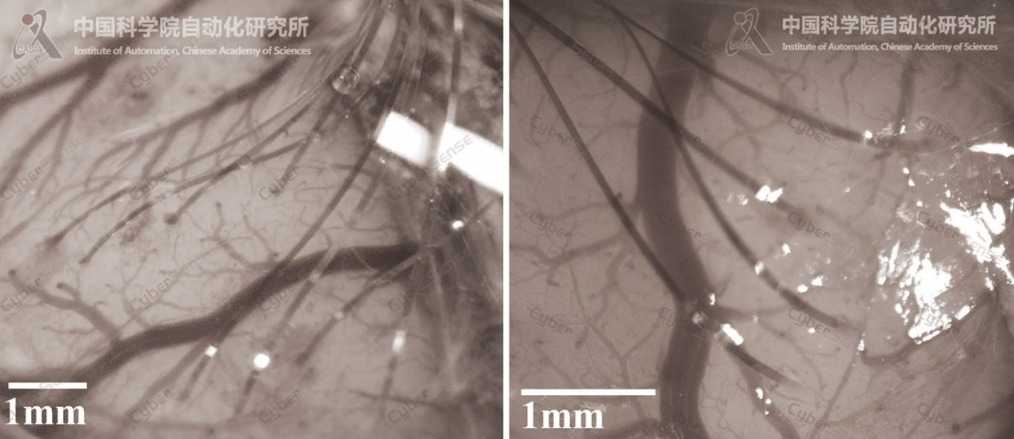

△动物大脑皮层多电极植入效果

CyberSense是“缝纫机”式柔性电极自动植入机器人,拥有多项自主知识产权,可灵活兼容不同规格的柔性微电极,应用于啮齿类、非人灵长类等动物的大脑皮层植入。该机器人能在其智能感知系统的引导下,以微米级的三维操作精度,将多根厚度≤10微米、宽度≤100微米的微丝状电极植入大脑皮层内,同时灵活地避让脑血管。由于其植入过程类似于缝纫机的工作原理,因此被称为“缝纫机”式植入。

植入后的柔性微电极能将大脑的神经电信号传导到微型芯片,由芯片处理并解析大脑的信息处理过程,同时也可通过微电流刺激电极触点附近的神经细胞,实现对脑活动的调控。目前,CyberSense已成功支持多种规格的柔性微电极植入,服务于脑机接口和神经电生理研究。